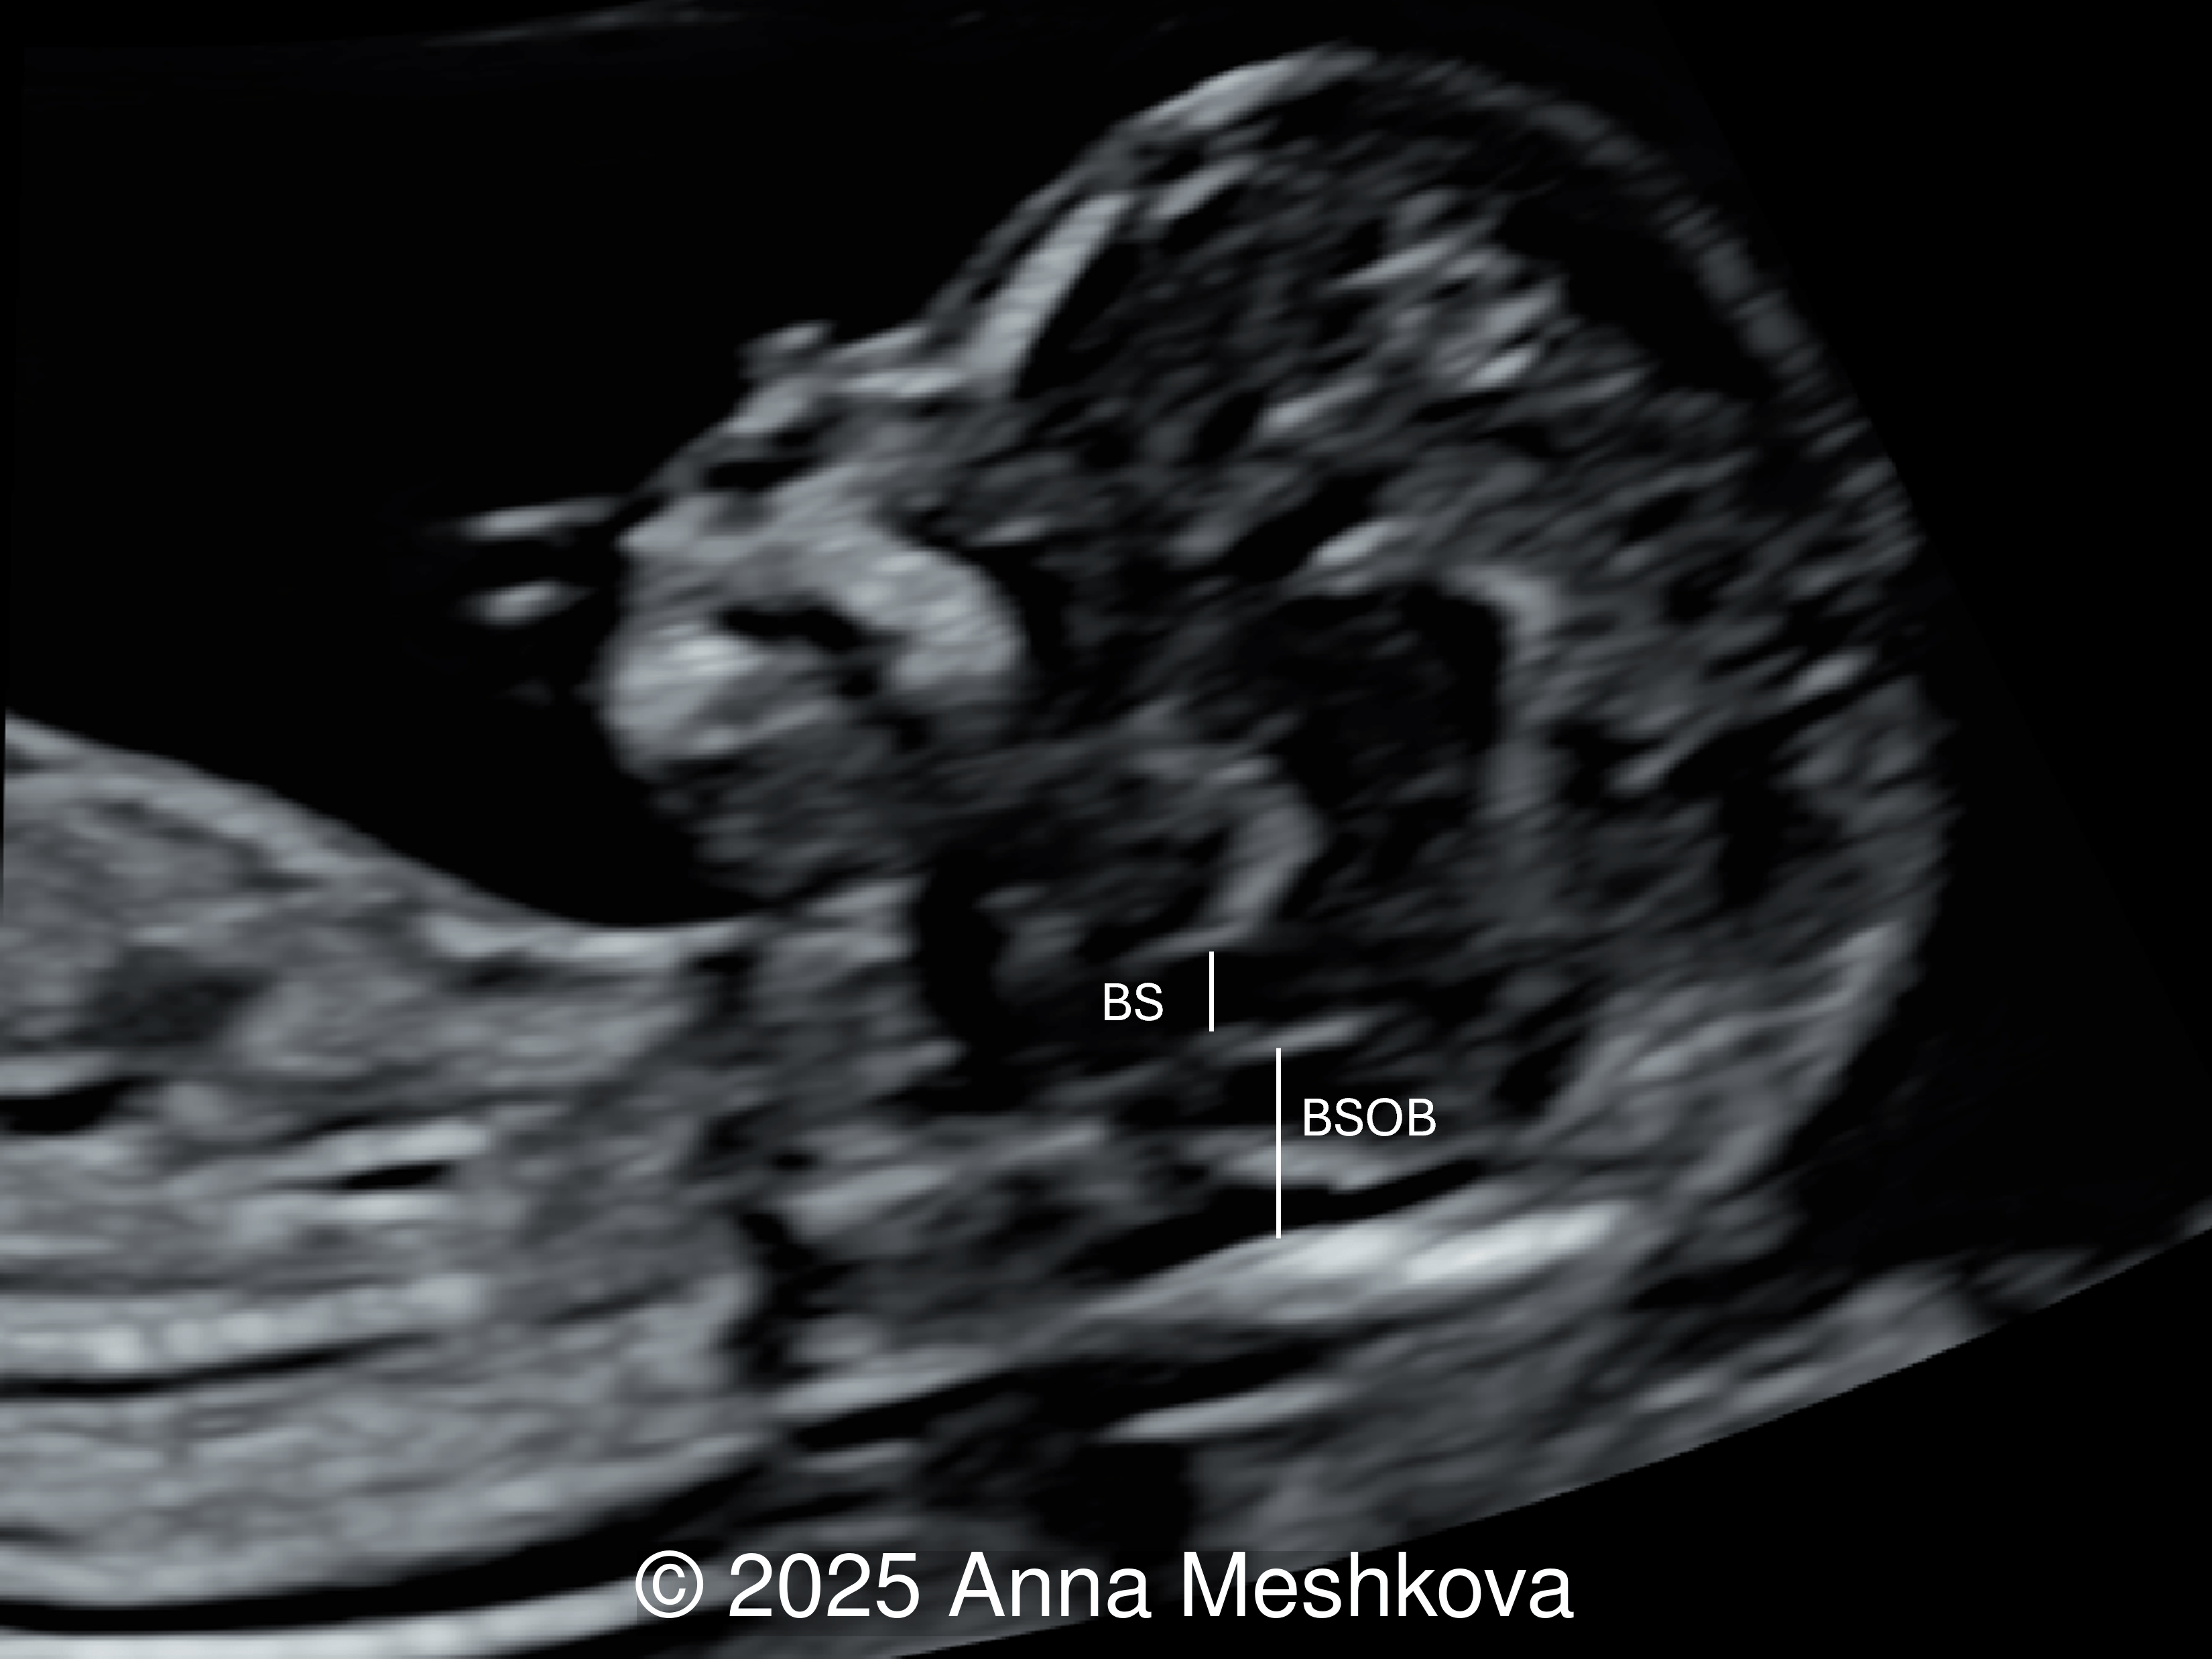

2.  Brainstem and Brainstem-Occipital Bone (BSOB) Distance measurements can suggest the diagnosis of open spina bifida. An increased brainstem diameter with reduced BSOB distance results in an elevated BS:BSOB ratio, which is a reliable indicator of open spina bifida.  In fetuses with open spina bifida compared to normal fetuses, the brain stem diameter (BS) is higher, the BSOB diameter is lower resulting in an increased BS:BSOB ratio [2].

In a normal fetus, the brainstem (BS) is relatively narrow and shorter in length than the brainstem–occipital bone (BSOB) distance.

Image 5 In a normal fetus, the brainstem (BS) is relatively narrow and shorter in length than the brainstem–occipital bone (BSOB) distance.

In a fetus with spina bifida, there is brainstem thickening and an increased BS:BSOB distance ratio

Image 6 In a fetus with spina bifida, there is brainstem thickening and an increased BS:BSOB distance ratio